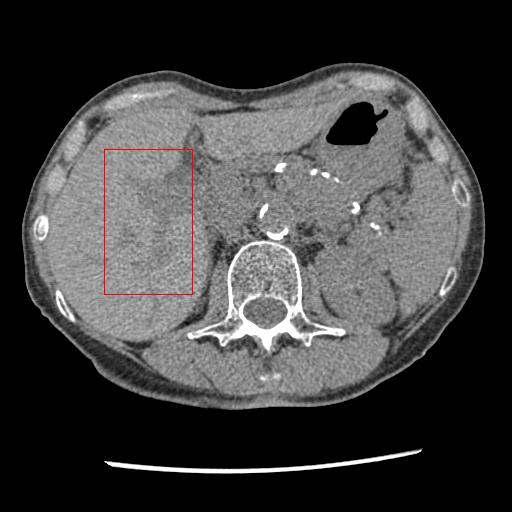

Figure 3: Comparison of denoising performance of different network. The boundary line of different organ extracted from the NDCT image is superimposed on other images. As seen, many pixels are missing around the boundary line in the output of M1

Refer to caption

(a) LDCT

(b) NDCT

(c) M1

(d) M2

(e) M3

Figure 4: Zoomed version of the ROI taken from the images of Figure 3. In the zoomed version missing boundary pixel is clearly visible in the output of M1.

This section systemically investigates the efficacy of every module proposed in this study. We considered three different networks; first, baseline model(M1), where the inverting block is replaced with dense block, and trained using minimizing mean square distance between two noisy observations(i.e. fsubscript𝑓\mathcal{L}_{f}). Next, two independent baseline model(one for forward mapping, one for reverse mapping) is jointly trained using a linear combination fsubscript𝑓\mathcal{L}_{f}, and rsubscript𝑟\mathcal{L}_{r}, similar to cycle consistent network paradigm. The forward mapping network is used for testing. We refer this model as M2. In both M1, and M2, we increased the depth of the network to make the representation power of these networks comparable with inverting network. Finally, the proposed method, referred as M3. Table 2 depicts the objective evaluation of the three networks using the D1 dataset. Both M2 and M3 use reverse mapping to regularize the network; the influence of the same in the denoising performance is evident from Table 2. Adding cycle consistency loss has improved the performance of the same baseline model significantly. The inverting network performed considerably better than the network M2. It improves PSNR by 0.23dB. As discussed in the above section, in case cycle consistency loss, an additional network is trained, but that does not always guarantee invertibility, whereas inverting network architecture inherently possesses reversibility, which acts as a strong regularizer. In Figure 3 we have shown denoising performance of different networks visually. To demonstrate the requirement of regularization, we first extract the boundary line of the various organ from the NDCT image and superimpose the boundary line on the output of different networks. As shown in Figure 3, many pixels around the boundary line of M1 network output are missing. Using the reverse mapping, the issue of the end-organ missing pixel is successfully overcome in M2 and M3. The granular pattern is also less present in the M3 than M2. The zoomed version of a ROI taken from the images of Figure 3 is given in Figure 4 for better perception. In Figure 5 we give an example of the performance of the invertible network in reverse mapping. Here, the predicted LDCT image is produced by using the predicted clean image of the forward mapping as the input for reverse mapping. As shown, the predicted noisy pattern is similar to the original noise pattern. The same streaking artifacts are present in both the noise pattern; also, the noise variance is different in the various spatial region depending on the signal intensity of the original CT image. It validates that the loss of information in reverse mapping is minimal. Due to the invertible network’s structural advantage, the network also preserves every information present in the input image in the forward mapping.